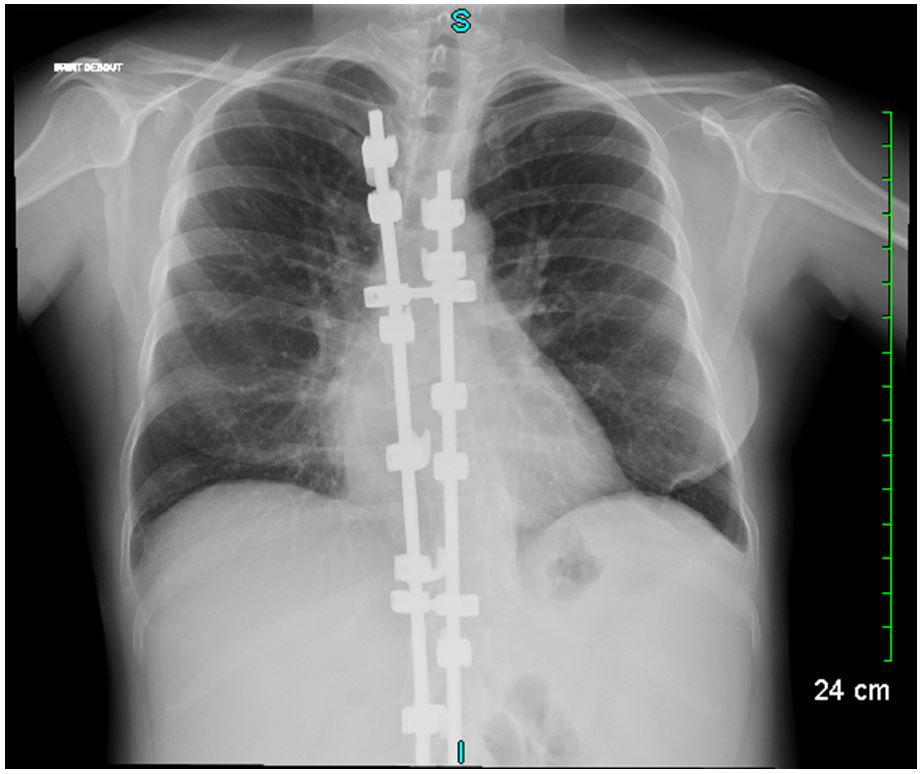

A 27-year-old female was referred to our department for management of an autoimmune haemolytic anaemia. Recent medical history included a diffuse large B-cell lymphoma at the age of 20 with negative Epstein-Barr virus (EBV) serology. She was considered in remission after four courses of rituximab, adriamycin, cyclophosphamide, vincristine, bleomycin, prednisone and intrathecal methotrexate, and consolidation with 2 infusions of methotrexate followed by successful autologous stem cell transplantation. During and after chemotherapy she had many bacterial infections and two episodes of herpes zoster reactivation. Examination of her childhood medical history found neonatal dwarfism and scoliosis with spinal osteosynthesis (fig. 1A), recurrent acute pulmonary and ear, nose and throat (ENT) infections with otitis media from the ages of 3 to 10 years, requiring placement of tympanostomy tubes at the age of 6 and adenoidectomy. The patient described frequent bronchitis and sinusitis requiring antibiotic courses two or three times a year, complicated by bronchiectasis (fig. 1B).

Figure 1 Chest X-ray showing scoliosis with spinal osteosynthesis and images of bronchiectasis.